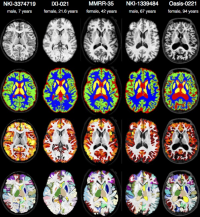

Interdisciplinary Bachelor/Master thesis in the domain of "Atlas Generation"

Within this project, clinically acquired magnetic resonance imaging (MRI) brain data of the past years is processed retrospectively. Using these data the primary task is to create a brain template with the Advanced Normalization Tools (ANTs) which will serve as a reference in diagnosis in neurodegenerative and psychiatric diseases. Beyond this, further tasks may vary depending on the individual skillset and type of work.